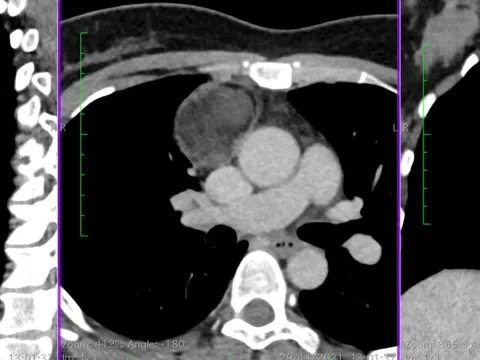

Người phụ nữ phát hiện ‘u quái’ có tóc, xương kỳ lạ: BS chỉ ra các dấu hiệu phát hiện

Người phụ nữ 54 tuổi được phẫu thuật nội soi loại bỏ "u quái" có tóc, xương ở trung thất, chèn ép các tĩnh mạch, phòng biến chứng nguy hiểm cho bệnh nhân.